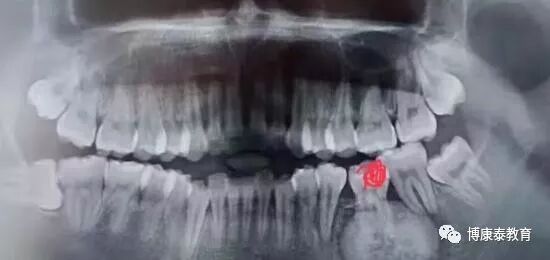

如果3天后仍有持续肿痛,就有必要做X线片检查,根据需要做进一步处理。

牙医要警惕,拔除松动牙,为什么一定要拍一个全景片?